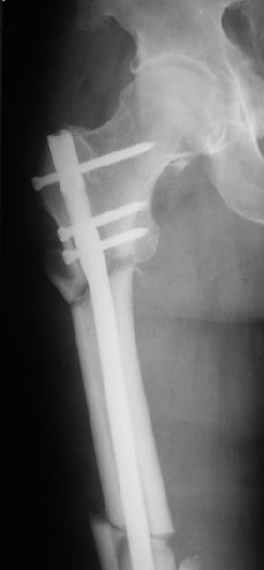

Женя, эта картинка показывает не оптимальное лечение вертельных переломов в моем представлении, а особенности дизайна упомяутого фиксатора.

В частности, его возможности при фиксации переломов проксимального отдела бедра - в сравнении с другими, имеюшими лишь по одному статическому и динамическому отверстию и с кондуктором для введения 2 винтов.

Это было года 2,5 назад, мы тогда еще уточняли возможности шинирования с угловой стабильностью гвоздем с поперечным расположением винтов при переломах проксимального отдела бедра. Пациенту не пришлось приобретать намного более дорогой рекон или проксимальный гвоздь. В приложении еще несколько примеров применения того гвоздя при высоких переломах бедра, в том числе с более латеральной точкой входа. Гвоздь изгибаем для этого.